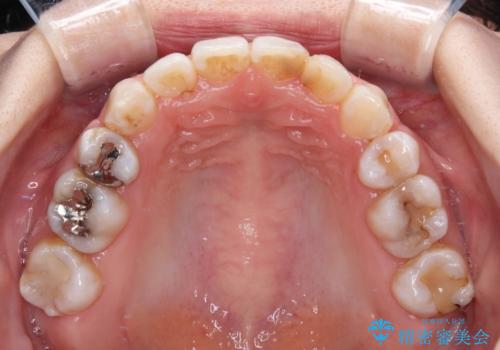

- 上下の八重歯と前歯のデコボコを気にして来院された患者様です。

右上と左下の八重歯が特に著しく、上顎正中が右側にシフトしていました。

デコボコが強いため小臼歯4本を抜歯し、上顎正中を左側に移動させるために補助装置を使用して、ワイヤー装置にて矯正治療を行うこととしました。